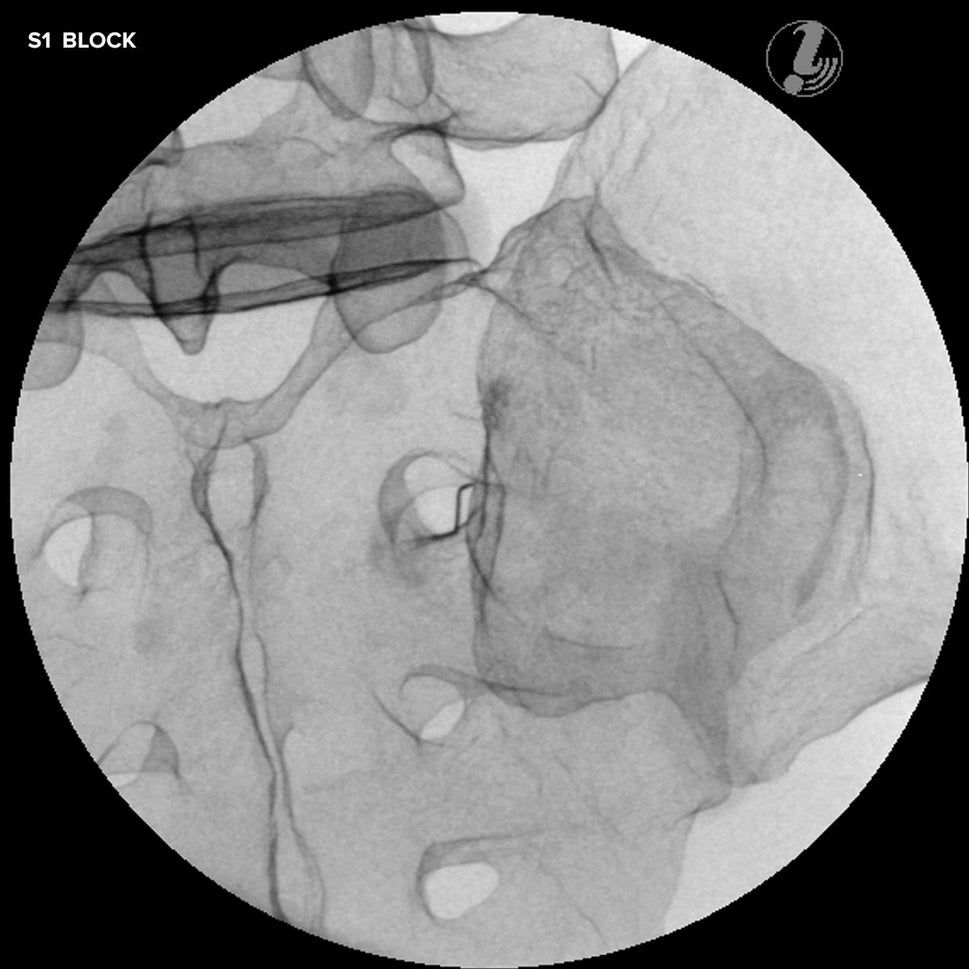

Epidural Injection Trainers

Train students and healthcare professionals in essential epidural injection skills using our highly realistic spine simulators, designed to enhance clinical training and procedural accuracy.

Our range of epidural injection trainers includes detailed anatomical models that replicate the lumbar and thoracic spine, providing a hands-on learning experience for anaesthetists, medical students, and pain management specialists. These advanced simulators allow users to practise needle placement, identify key anatomical landmarks, and develop proficiency in administering epidural and spinal anaesthesia with confidence. Ideal for medical schools, hospitals, and professional training programmes, these epidural trainers support skill development in regional anaesthesia, labour pain management, and spinal procedures. With lifelike materials that simulate real patient responses, our models offer a realistic and immersive training experience.